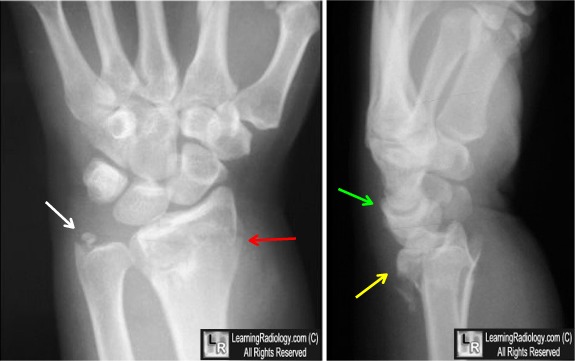

<br /><br /><br />4) Hutchinson - внутрисуставной перелом шиловидного отростка лучевой кости.<br /><br />

<br /><br /><br />Схематически эти типы переломов выглядят так:<br /><br />